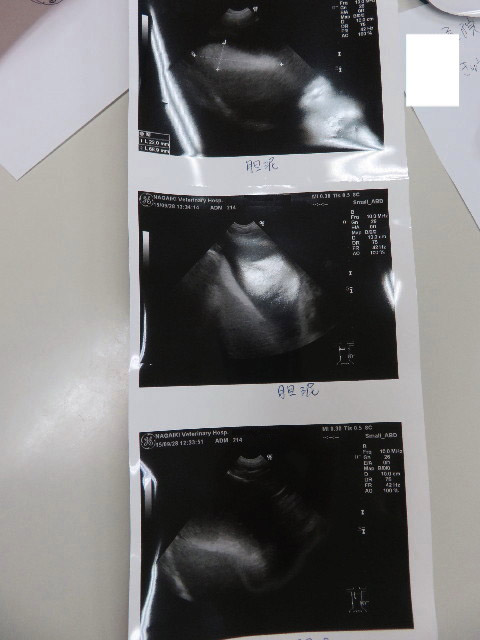

●エコー

○膀胱粘膜が肥厚し、かつ膀胱内部がギザギザのところも。

膀胱粘膜が炎症を起こしているという事は膀胱炎かもということで検尿しました。

結果、おしっこはキレイ(ほんの少し白血球がでている)ですが、結果としては膀胱炎による炎症でしょうとの事で消炎剤(バキソ10mg)を1日1カプセル14日飲むことに。(抗生剤は飲みません)

ひどくはなくて、これから注意が必要な膀胱炎とのことです。

※今までに、ひどい膀胱炎の最中にエコーをしたことがありますが、常に膀胱はきれいで、今回のように膀胱粘膜肥厚や、内部がギザギザになってしまったのは初めての事です(汗)

ということは、前回9月15日からわずか14日で、ひどくはないですが【23回目の膀胱炎】になってしまったということです(°_°)

○胆泥は、浮遊しているのは少なくなりましたが、底にたまっているのはあいかわらず。

胆泥は炭水化物と脂肪をひかえるとよいので、ケトン食に期待したいです。

(お肉は多く食べるので脂肪はどうしても多くなってしまうのが困りものですが)

今回のエコーの感じからすると、スカパールよりウルソのほうがよさそうなのでこのままウルソを継続します。

○腎臓は問題ありませんでした。